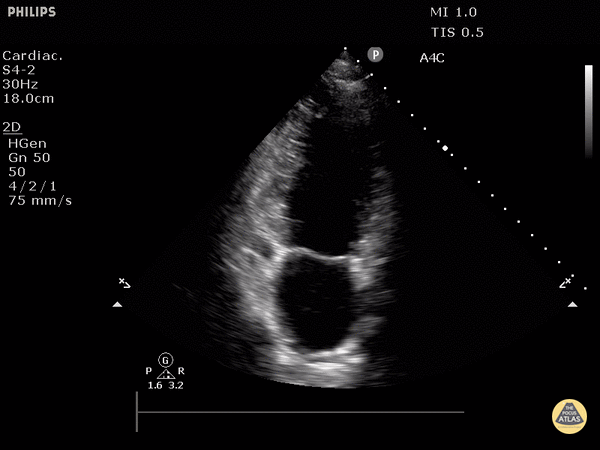

View: Unspecified Parasternal Long Axis Parasternal Short Axis Apical Four-Chamber Subcostal Four-Chamber Subcostal Inferior Vena Cava Right Upper Quadrant Left Upper Quadrant Suprapubic Longitudinal Suprapubic Transverse Subxiphoid Anterior Thoracic Phrenic

Notes: actually 2 chamber